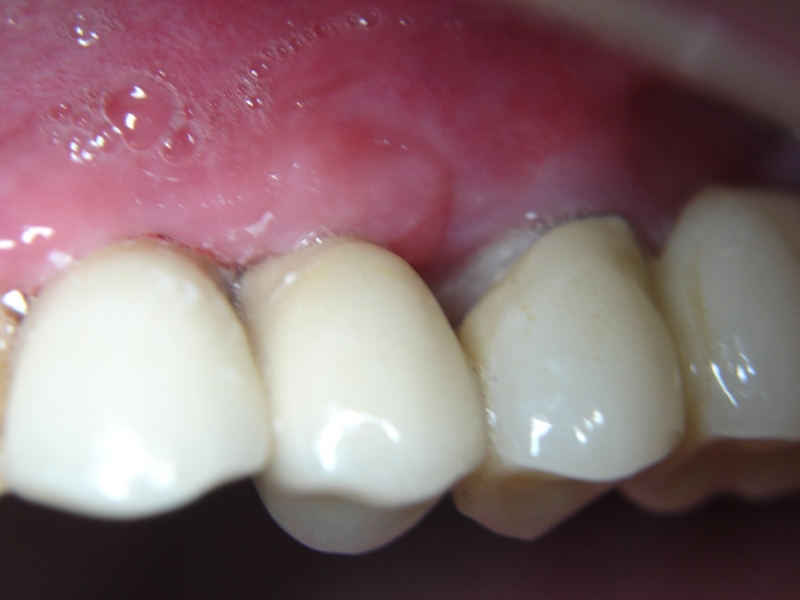

Initial view of the case. Discoloration of 1.1 and mild class I gingival recession